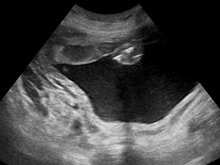

Polyhydramnios (polyhydramnion, hydramnios, polyhydramnios) is a medical condition describing an excess of amniotic fluid in the amniotic sac. It is seen in about 1% of pregnancies.[1][2][3] It is typically diagnosed when the amniotic fluid index (AFI) is greater than 24 cm.[4][5] There are two clinical varieties of polyhydramnios:

During the pregnancy, certain clinical signs may suggest polyhydramnios. In the mother, the physician may observe increased abdominal size out of proportion for her weight gain and gestation age, uterine size that outpaces gestational age, shiny skin with stria (seen mostly in severe polyhydramnios), dyspnea, and chest heaviness. When examining the fetus, faint fetal heart sounds are also an important clinical sign of this condition.